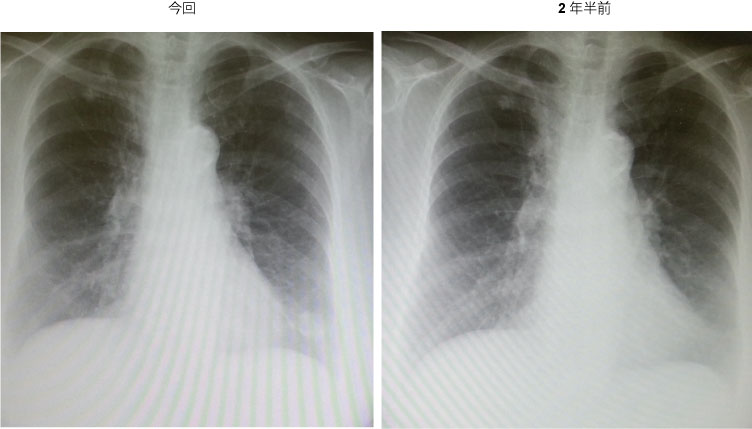

76歳。女性。糖尿病治療中。3年前の胸部CTで腫瘤指摘されず。2年半前の胸部Xpで腫瘤指摘されず。それ以降胸部Xpは撮っていなかった。今回、スクリーニング目的で胸部Xp撮影。

胸部Xp:左下肺野腫瘤